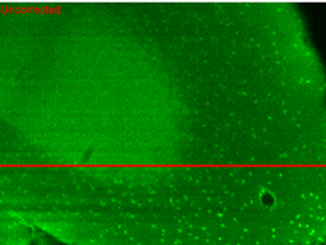

Ricercatori dell’Istituto di fotonica e nanotecnologie del Cnr di Padova hanno messo a punto un innovativodispositivo di ottica adattiva per micro… […]